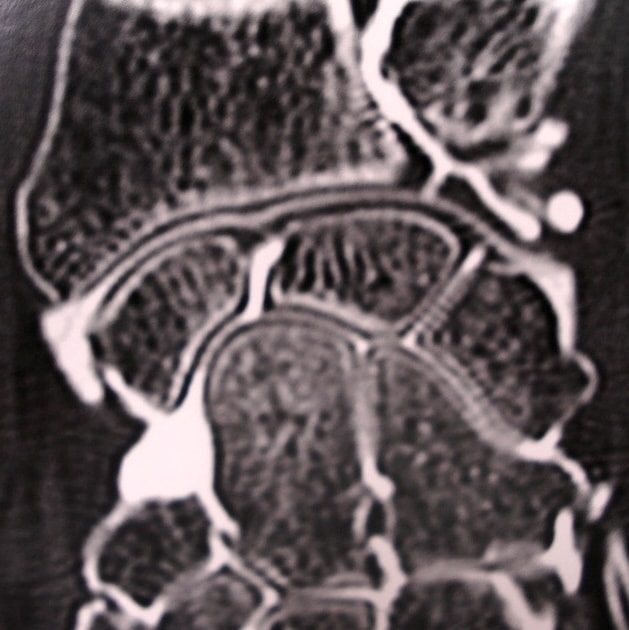

Arthroscanner perforation ligament triangulaire poignet

Arthroscanner montrant bien la perforation complète du ligament triangulaire